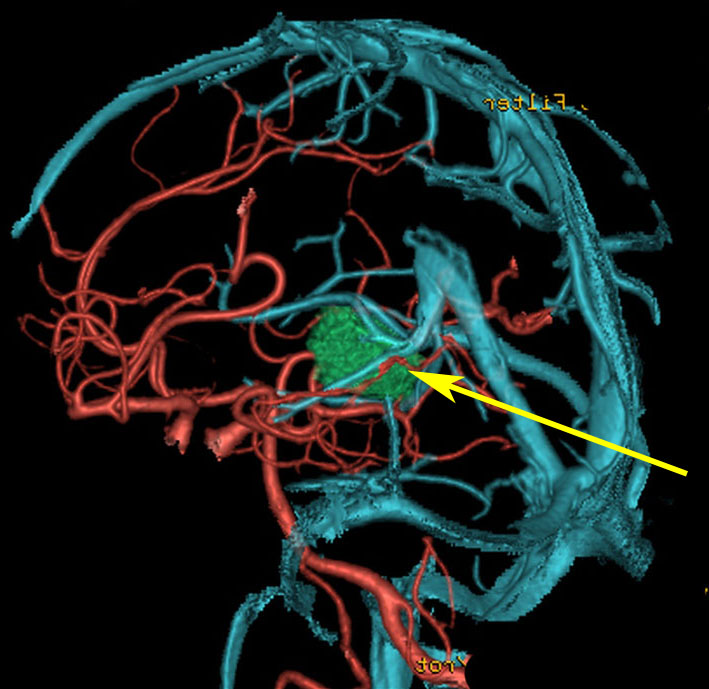

松果体腫瘍へのOTAのルートです。occipital transtentorial apporachというのは黄色の矢印に沿ってガレン大静脈の下に入る方法であり,そこから松果体部を通って第3脳室内へ直線的な視野が展開します。

一方,赤の矢印に沿ったルートは parieto-occipital transtentorial approachです。このルートでは内大脳静脈 internal cerebral veins を見ることがかなり難しいです。更に,第3脳室に入るためには脳梁膨大部 spleniumを切断する必用があります。ただし,小脳上部や第4脳室を見るときにはparietal寄りのルートを使います。

OTAでこの奇形腫を見ようとする場合に,テントを静脈洞交会の低い位置まで切断しなければ,直静脈洞の横から松果体部をみることはできません。また,黄色の矢印の方向に視野が入るので,まず最初に邪魔になるのは小脳上極です。上小脳層を左右ともに十分剥離すると,小脳が可動化して,その向こうに,precentral cerebellar veinが見えます。このveinをガレン大静脈への流入部から小脳前面に沿って剥離していくと,小脳上極がさらに可動化して松果体への視野が開ます。

松果体腫瘍の手術では,中脳背面を見る必要があります。特に上丘とそれに連続する後交連 posterior commissureを十分に観察するために周囲組織の剥離を行います。具体的には迂回槽と下丘の周囲のクモ膜組織を剥離します。対側中脳と迂回槽を見る時に妨げになるのが,緑の矢印で示した直静脈洞です。テントが長く切断してあって直静脈洞が大脳鎌と一緒に動かせると対側を見るのがとても簡単になります。